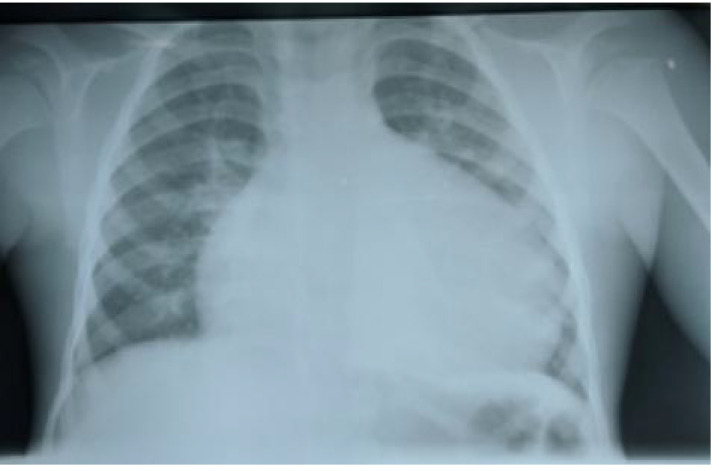

Case presentation: We report the case of a seven-year-old boy who had a diverting Devine descending colostomy for high ARM and was followed up until he had a posterior sagittal anorectoplasty (PSARP). He thereafter re-presented with complaints of intermittent constipation which was not responsive to rectal washout necessitating a levelling colostomy and subsequently an abdominal Swenson's pull-through procedure. Postoperative period was complicated with a colo-urethral fistula (Urethroscopy findings https://youtu.be/lxzyp1uHFpE?feature=shared) necessitating multiple staged surgeries. He has been followed up in clinic for over one-year post-surgery with complaints relating to frequent bowel motion, passes well-formed stool about three times daily. We report a rare case of HD associated with ARM, highlighting the delay in diagnosis, the associated morbidities requiring multiple surgeries and the challenges encountered in the management of the patient.